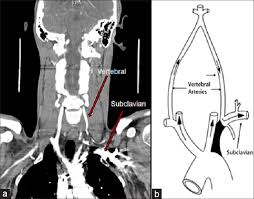

Subclavian steal syndrome definition. Look it up now. Subclavian Steal Syndrome SSS is a condition that results from subclavian artery stenosis proximal to the origin of the vertebral artery. Subclavian steal syndrome implies the presence of significant symptoms due to arterial insufficiency in the brain ie vertebrobasilar insufficiency or upper extremity which is supplied by the subclavian artery figure 1.

Exercising the arm causes the blood flow to reverse and the subclavian artery steals blood from the vertebral. Subclavian steal refers to a syndrome of symptoms relating to arterial insufficiency in a branch of the subclavian artery stemming from flow reversalattributable to occlusive disease in the subclavian artery proximal to that branch that is usually atheroscleroticin cause. The physiology diagnosis and treatment of.

Subclavian Steal Syndrome SSS which is the reverse flow from vertebral artery to subclavian artery was first described in 1977 with an incidence of 044. In medicine subclavian steal syndrome also called subclavian steal phenomenon or subclavian steal steno-occlusive disease is a constellation of signs and symptoms that arise from retrograde flow of blood in the vertebral artery or the internal thoracic artery due to a proximal stenosis andor occlusion of the. A clinically significant reduction in blood supply to the BRAIN STEM and CEREBELLUM ie VERTEBROBASILAR INSUFFICIENCY resulting from reversal of blood flow through the VERTEBRAL ARTERY from occlusion or stenosis of the proximal subclavian or brachiocephalic artery.

A hemodynamic classification into four types of subclavian artery stenosis is also presented. They have been successfully treated by angioplasty of the subclavian artery. Early modifications of the flow in the vertebral artery due to subclavian artery stenosis are presented.

Subclavian steal syndrome is defined as stenosis or occlusion of the subclavian artery proximal to the origin of the vertebral artery with consequent reversal of blood flow in the vertebral artery to supply the distal subclavian artery resulting in neurologic symptoms. The symptoms of cerebral vascular insufficiency not enough blood to the brain when the patient exercises an arm due to obstruction of the subclavian artery before the origin the takeoff of the vertebral artery. In summary subclavian steal syndrome is blood flow reversal in vertebral arteries usually caused by severe stenosis of the subclavian artery or innominate artery.